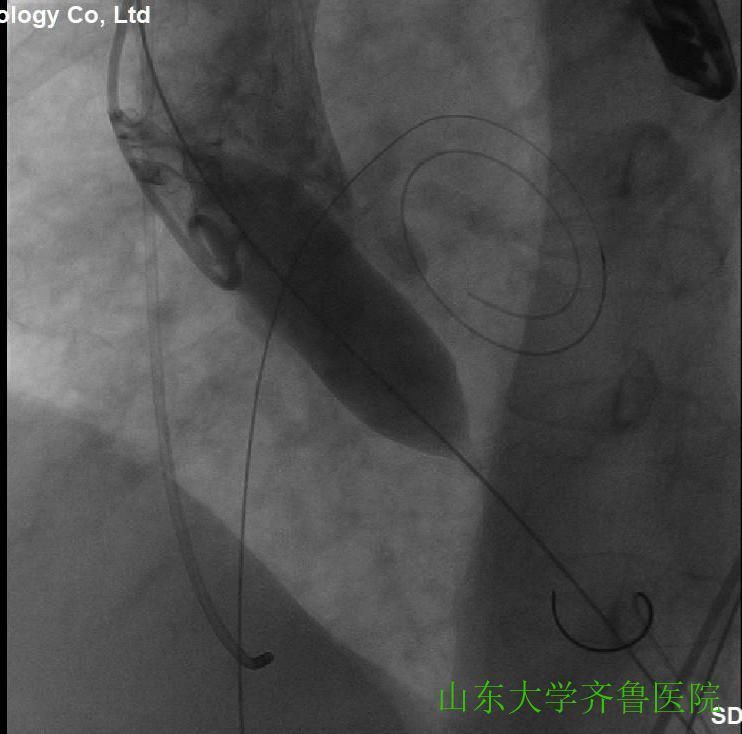

在手术室护士长翟永华及其护理团队、麻醉科吴剑波主任医师和杨绍忠主治医师的大力支持下,由心血管外科谷兴华主任医师、急诊心内科李传保主任医师、心内科安贵鹏副主任医师、心血管外科孙厚荣副主任医师及刘凯副主任医师、心脏超声室刘艳副主任医师和曹媛主治医师、放射科邵汉宏技师等在医院复合(Hybrid)手术室行一站式经导管主动脉瓣置换术(TAVR)+经皮二尖瓣球囊扩张成形术(PBMV)。手术先常规经颈静脉于右心室放置临时起搏导线并放置经食道TEE探头,行主动脉根部造影,明确主动脉瓣环平面、主动脉瓣钙化及返流情况(图1),导丝跨瓣入左心室并更换猪尾导管,测主动脉瓣跨瓣压差为76mmHg。选用24mm的擎源二尖瓣扩张球囊扩张2次,二尖瓣口面积由0.78?扩大至1.43?,并且二尖瓣无返流(图2)。选用20mmNuMed球囊,临时起搏心率180次/分,扩张狭窄的主动脉瓣(图3),应用26mmVenusA主动脉瓣介入瓣膜,准确定位、释放,造影、多体位透视及术中TTE显示介入主动脉瓣膜形态满意、无瓣周分流(图4-6)。术后即刻主动脉瓣最大跨瓣压差将至2mmHg。手术顺利,手术用时1小时40分钟,术后患者安返心脏外科监护病房。

图3主动脉瓣球囊20mm扩张,显示左右冠状动脉,无主动脉瓣返流